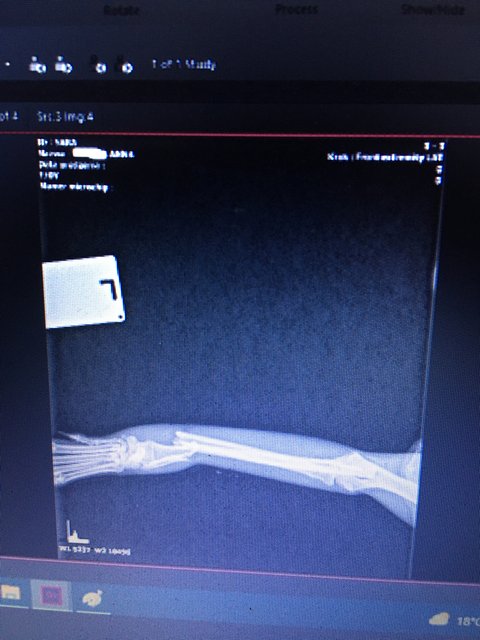

WiosnaA Posted July 3, 2022 Posted July 3, 2022 Na wsi z ruchliwą trasą przelotową ktoś wyrzucił sunię:( We czwartek potrącił ją samochód, w szoku odbiegła, schowała się w zaroślach obok mojej działki. Wieczorem podlewając ogródek usłyszałam szelest, popiskiwanie i zauważyłam sunię jak próbuje wyjść z wysokiego zielska, pupa chwiejna, ledwo stała na trzech łapkach, jedna zwisała bezwiednie. Syn przyniósł do domu,dałam p./bólowy i musieliśmy czekać do rana. W tym całym nieszczęściu mieliśmy szczęście, że w piątki bywa w naszej Profesor Adamiak-ortopeda, od razu bez czekania nas przyjął, zbadał,zabezpieczył, a w sobotę przyjechał specjalnie do lecznicy, żeby poskładać łapkę. Na szczęście miednica nie jest połamana,a tylko obolała od uderzenia. Zabieg jest drogi, ale czas gra rolę, pies młodziutki i życie przed nim ,decyzję o ratowaniu łapki podjęłam od razu. Kochani,proszę Was ogromnie o pomoc w znalezieniu domowego miejsca dla suni. Dzwonię,pytam,proszę, i nie mam gdzie jej umieścić . Bardzo,bardzo potrzebuję sunię gdzieś ulokować, ponieważ moja Majka dostaje amoku na jej widok i nie na żarty paszczę otwiera:(. Tak było jeszcze przed wypadkiem, gdy sunia pojawiała się przy naszej posesji na posiłek. Musiałam Majkę chować do domu, ponieważ i sunia zaczynała wdawać się z Majeczką w pyskówki. Wybitnie nie przypadły sobie do gustu. Z tego też powodu i zabezpieczyć suni na posesji nie miałam jak,bo część ogrodu większość dnia jest wyłączona dla psów ze względu na budowlańców i otwartą bramę. Nie spodziewałam się takich reakcji po Majce,ale odżyła u nas i jest szefową stada. Gdy się dowiedziałam, że sunia nie jest psem właścicielskim ze wsi, zaczęłam szukać jej domu,fundacji,dokarmiałam...pomóc nie zdążyłam:( Sunia ma założone śruby w łapce, przez 10 tygodni musi przebywać w klatce, mieć względny spokój, a moje psiaki nie są zwyczajne, bezproblemowe, każdy po przejściach i wymaga odpowiedniego podejścia, są natomiast zgrane i wszędzie są razem. Mam otwartą przestrzeń w domu i nie mam jak psów izolować, nie zamknę Majeczki w kojcu na długie tygodnie,ona już swoje odsiedziała, musiałabym z nią razem i Marcelka zamykać,bo są nierozłączni, a jemu to byłaby tragedia:( Od roku mam na działce prace budowlane i wiek nie jest słuszny na takie przedsięwzięcia, które rozpoczęłam, muszę jednak jakoś dokończyć. Na żadną pracę z psami zwyczajnie nie jestem teraz w siłach. Proszę i błagam pomóżcie mi znaleźć Sarze bezpieczny kąt:( Jeżeli ktoś mógłby wesprzeć nas finansowo byłabym ogromnie wdzięczna. Koszt I wizyty u weta ze zdjęciami rtg- 347zł Koszt zabiegu 1614zł Przez lecznicę sunia została potraktowana ulgowo,ale koszty i tak są duże. Sara przed wypadkiem, 1 Quote

WiosnaA Posted July 3, 2022 Author Posted July 3, 2022 W łapce zbiera się płyn, p.Doktor sporo dziś wycisnęła ,( na razie mam się nie martwić,tak zdarza się po zabiegu), po konsultacji z Profesorem dołączony został lek p./zakrzepowy Apo-Pentox, sunia dostała dodatkowy zastrzyk(nie pamiętam nazwy). Sunia je ,pije, ale ciężko dłuższą chwilę jej ustać na łapkach.Wynosząc na siku zrobi parę kroków i łapki drżą, kładzie się, leży spokojnie w klatce, odpoczywa. Quote